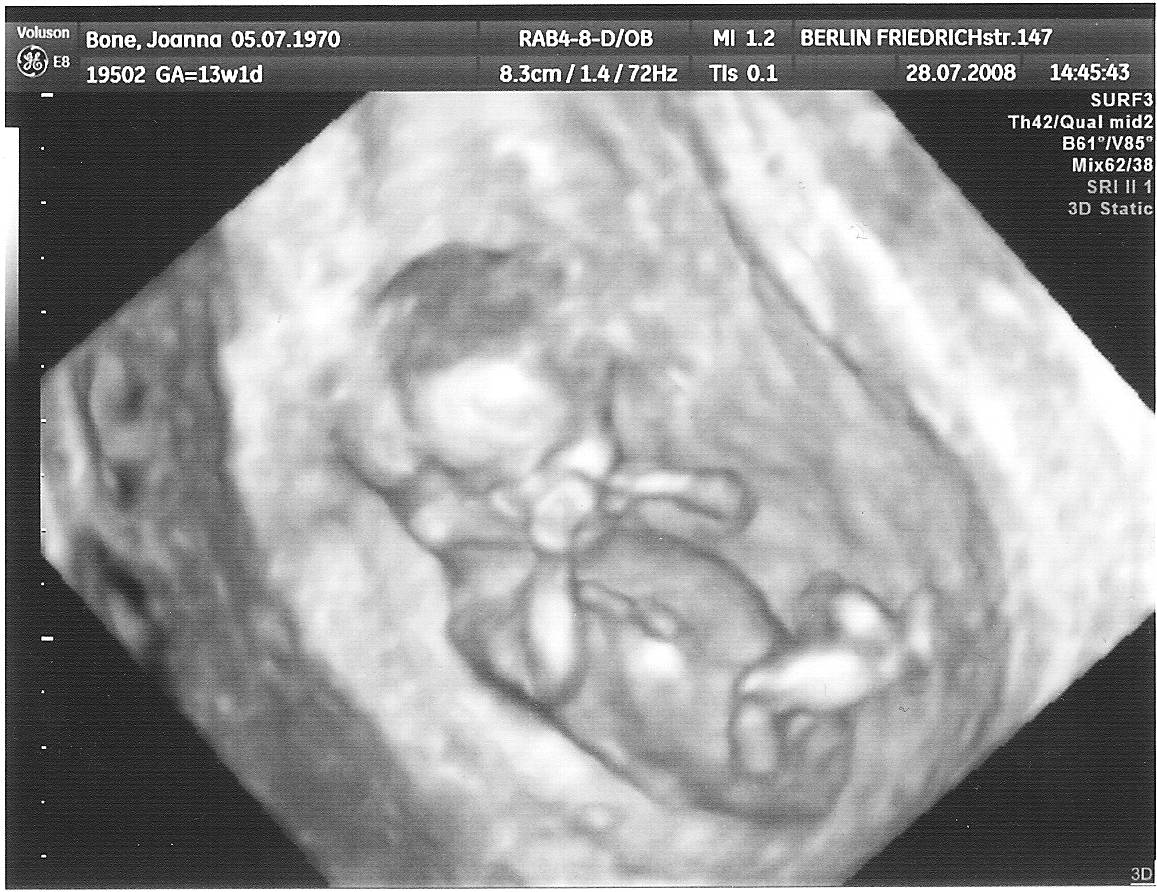

Ja też się muszę pochwalić :), miałam dzisiaj pierwsze USG, dzidzia ma 3cm :), bardzo machała rączkami, słyszałam serduszko...

usg1.jpg